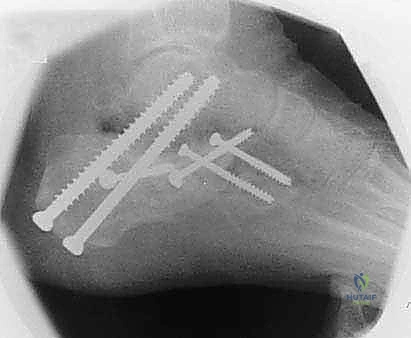

2. التصوير بالأشعة السينية (X-rays) مع تحمل الوزن

صور الأشعة السينية هي الخطوة الأولى. يطلب د. هطيف صوراً بوضعيات محددة (أمامية خلفية، جانبية، ومحورية Harris view) لتقييم:

* زاوية بوهلر (Böhler's angle) وزاوية جيسان (Gissane's angle) لتقييم فقدان الارتفاع والانخساف.

* مدى اتساع الجدار الجانبي.

* علامات التهاب المفاصل (تضيق المسافة المفصلية، تكون نتوءات عظمية، وتصلب العظم تحت الغضروف).